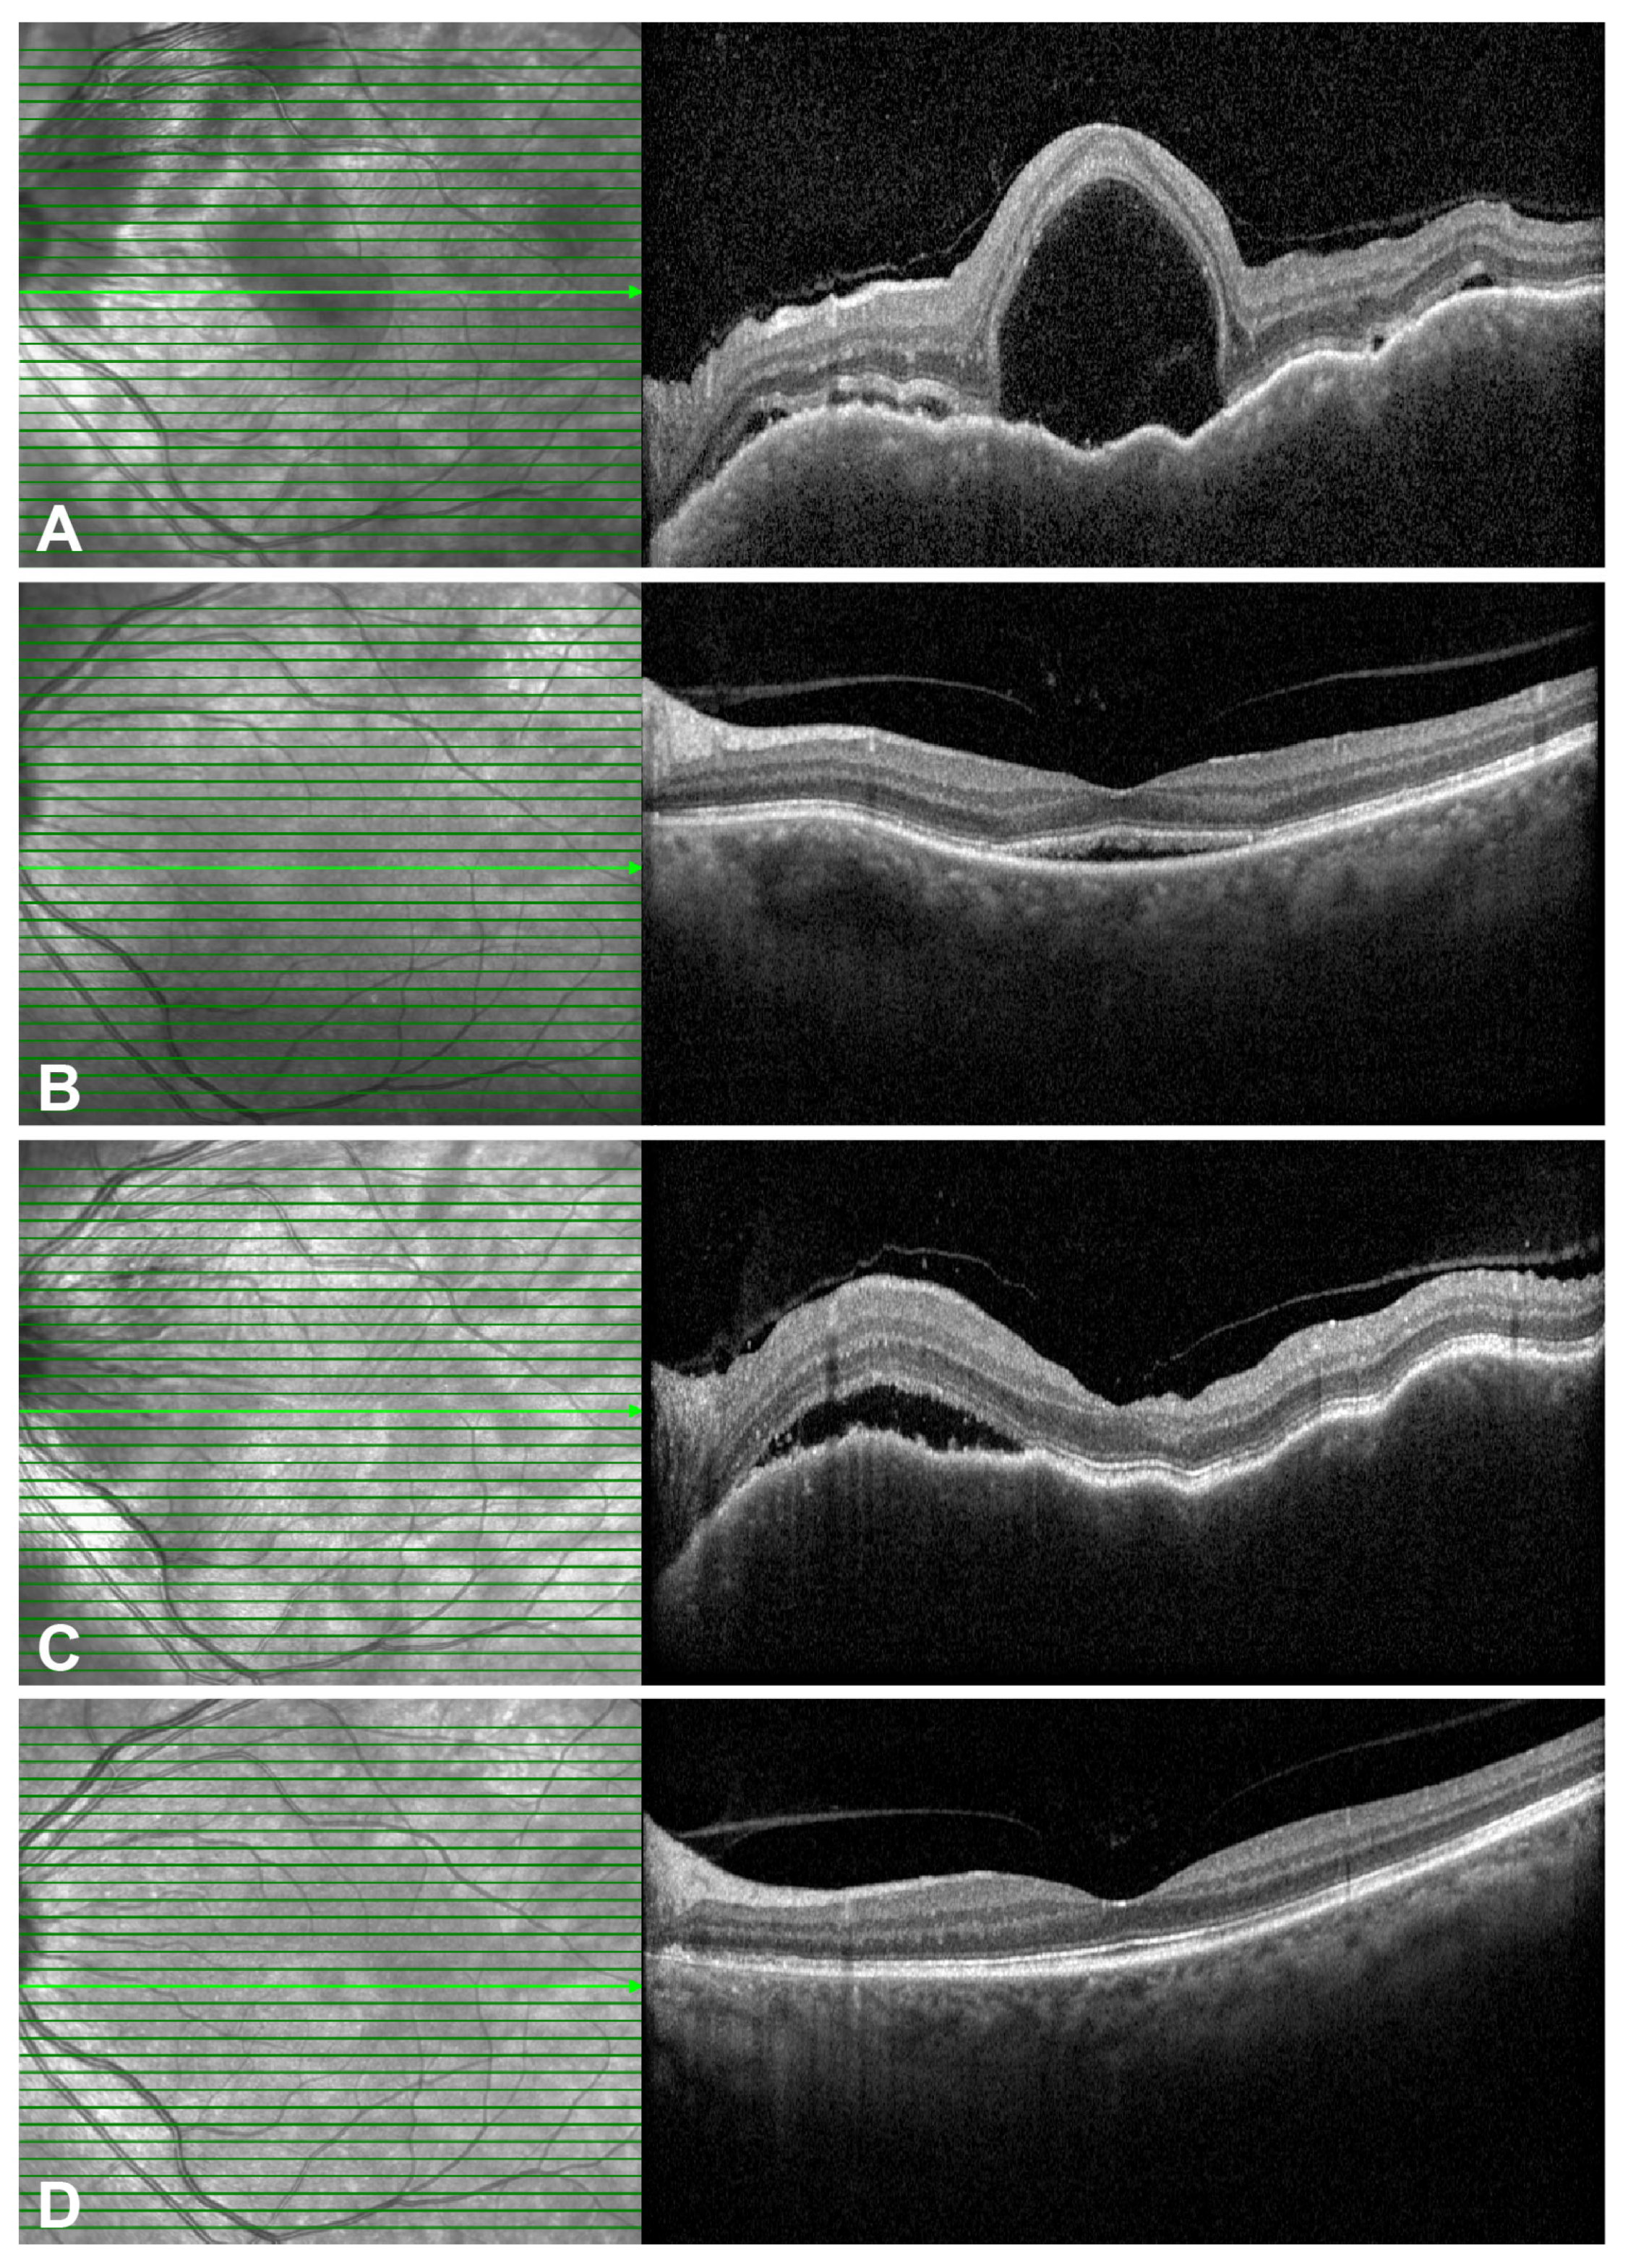

2.3. Representative Cases